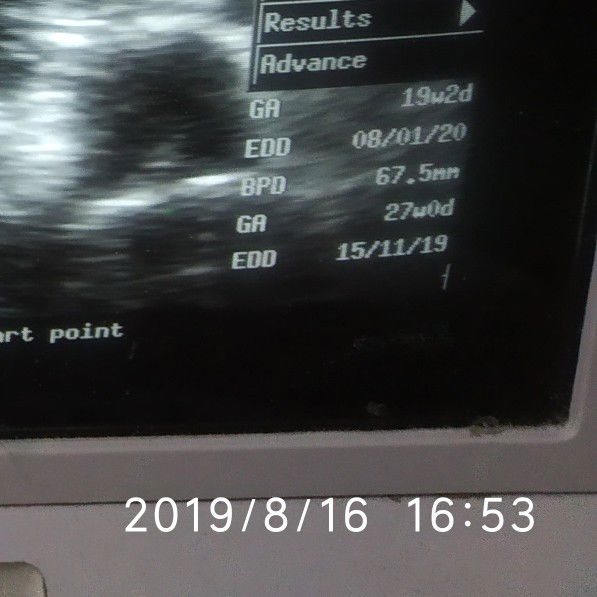

Bun ada yg paham nggak yaa.. kan usia kandunganku 28w tapi pas usg kok hasilnya 27w sama 19w. . yang bner mana ya.. jadi takut.. dokternya sihh bilang 27w . Tapi aku ya takut aja soale ada tulisan 19w?barang kali ada yang paham bun..